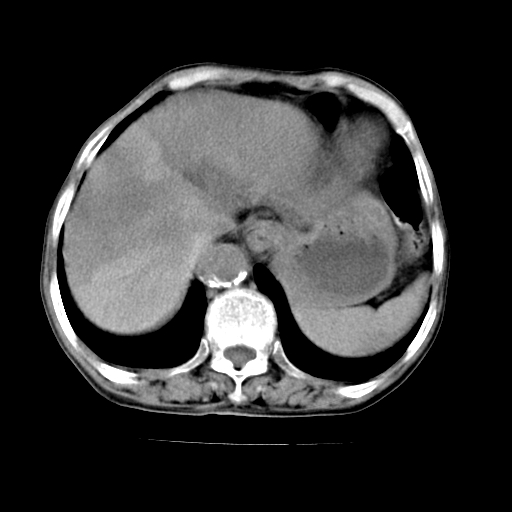

标题: CT19149:女,68岁,腹胀、恶心两周。 [打印本页]

标题: CT19149:女,68岁,腹胀、恶心两周。

女,68岁,腹胀、恶心两周,先做ct平扫,当时家属不同意强化,6天后家属要求增强扫描。

1、胃窦癌; 2、局灶性脂肪肝。

1、胃窦癌?建议行胃镜!; 2、局灶性脂肪肝。

1.局灶性脂肪肝;2.胃窦癌可能,建议行进一步检查。

不均匀脂肪肝,胃腔改变须结合钡餐或胃镜观察

1)局灶性脂肪肝。2)胃窦癌可能,建议行胃镜检查。